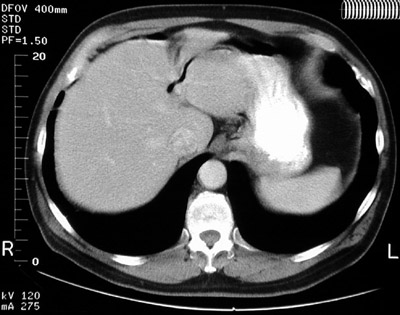

The

dark area

in the left lobe of liver seen in this abdominal CT scan represents pneumobilia, which rarely can complicate biliary tract lithiasis or neoplasia with fistula formation. Contrast fills the

stomach

. The

spleen

is present at the left.